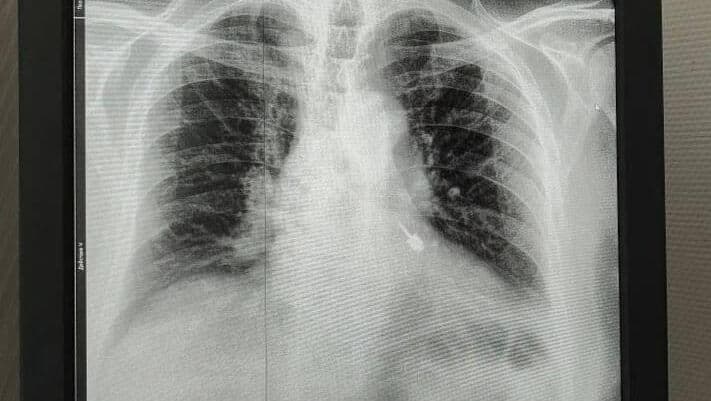

По данным ведомства, мужчине во время лечения зубов в частной клинике в дыхательные пути попал стоматологический бур. Почувствовав дискомфорт, он обратился к медикам. На приёме в Мытищинской больнице бур был обнаружен в левом бронхе. Требовалась срочная операция.

Стоматологический бур, извлеченный из бронхов пациента, проходящего лечение в частной клинике в Подмосковье